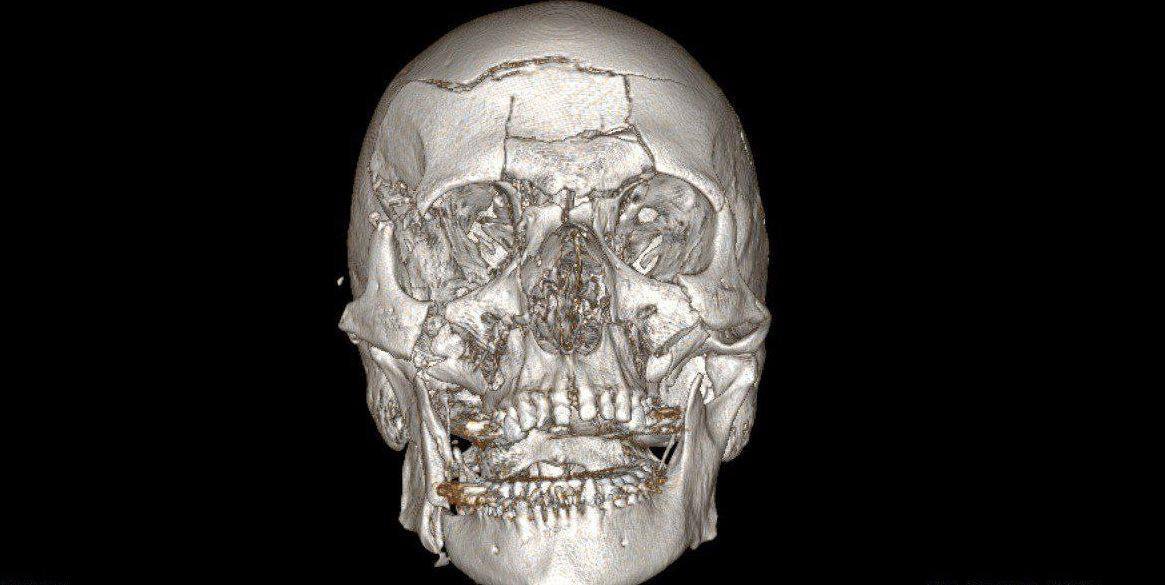

В Жуковскую больницу доставили 44-летнего мужчину в тяжёлом состоянии после падения со снегохода. У него диагностировали многооскольчатый перелом нижней зоны лица и множественные переломы лобной кости.

На нейрохирургическом этапе специалисты удалили костные отломки лобной кости, провели ревизию лобной пазухи и закрыли дефект твёрдой мозговой оболочки. Затем челюстно-лицевые хирурги вернули на место костные фрагменты и восстановили лобную кость, часть глазницы, контуры орбит, верхнюю челюсть и правую половину нижней челюсти, зафиксировав их титановыми минипластинами.